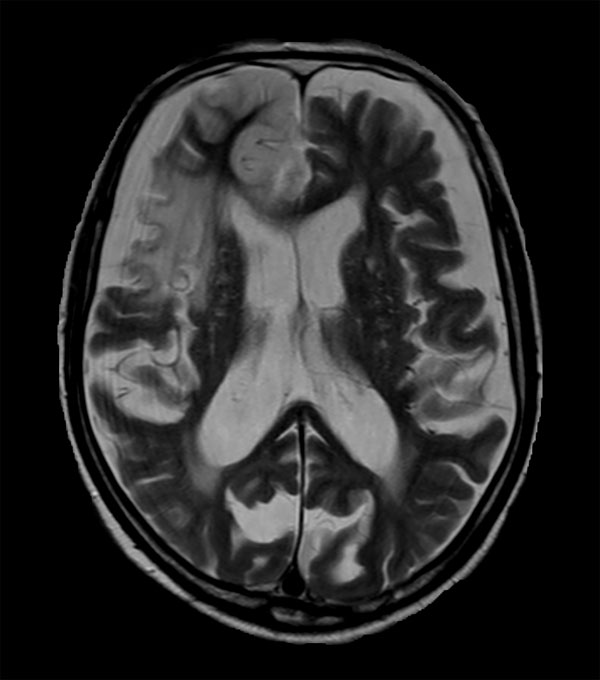

Acute stroke. Patient was brought to the first aid and directly transferred to the MRI unit. Axial studies were performed to get an overview of the stroke. Total study time is 9 minutes.

Axial T2w TSE

Axial T2* FFE